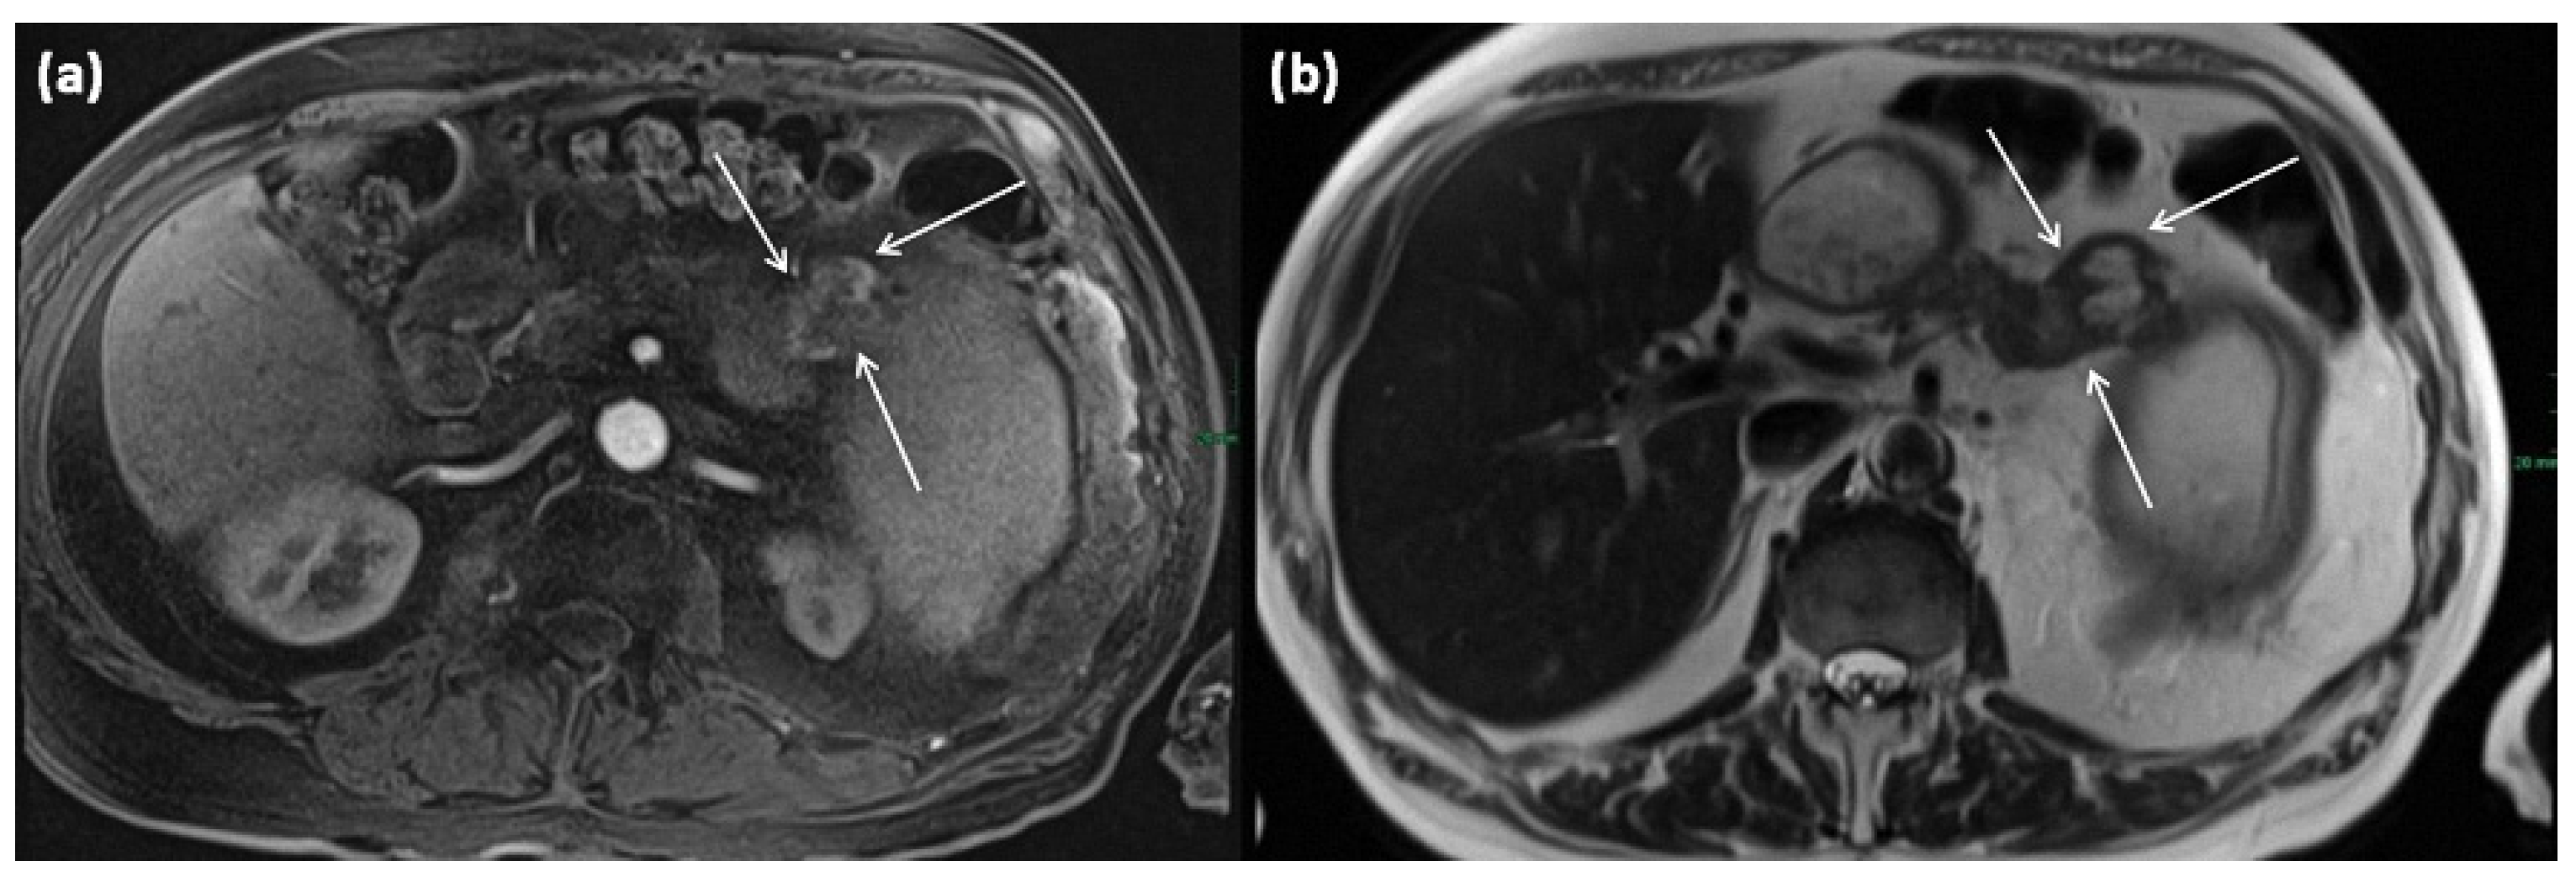

3.5.2. Branch Duct IPMN